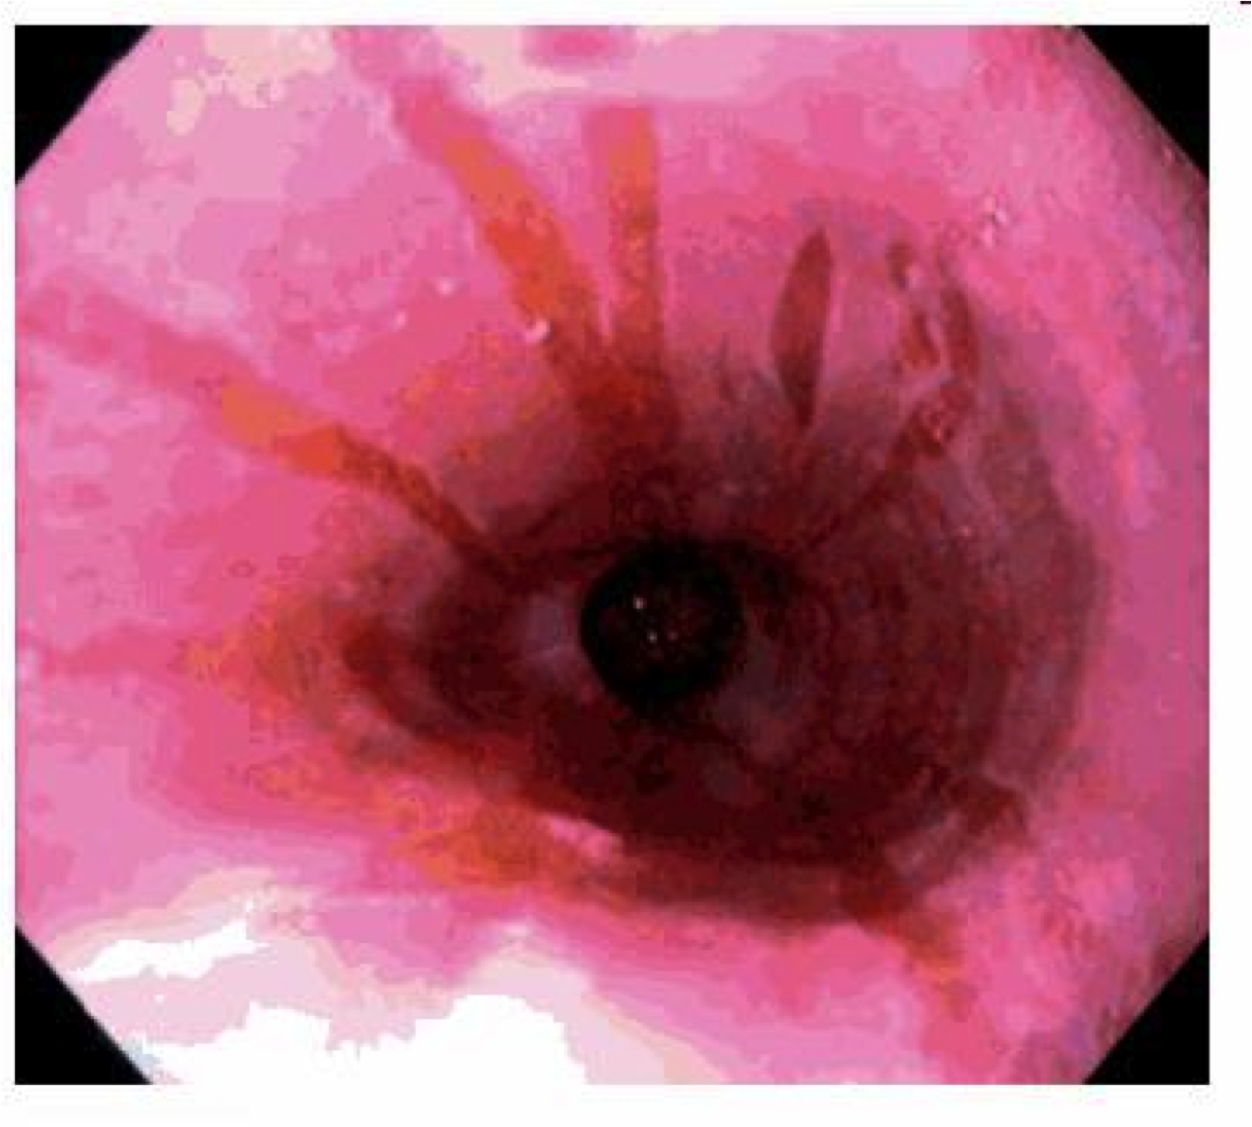

GERD

Hyperemia, vertical linear streaks represent superficial mucosal erosions/ulcers

GERD on bottom